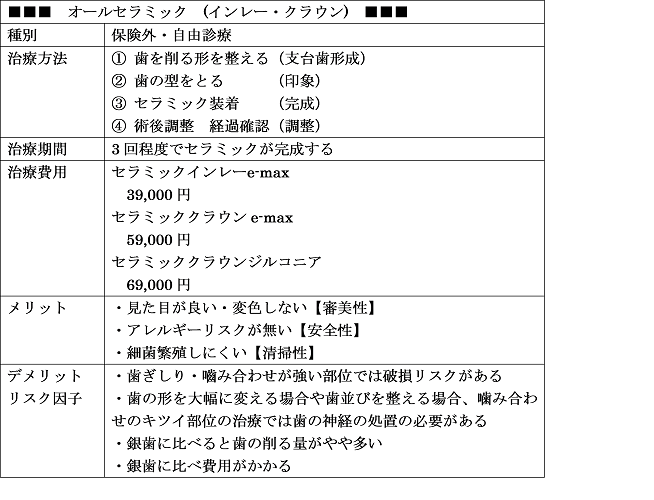

①きわだつ白さの汚れにくく耐久性抜群【プレミアムセラミックジルコニア】

②透明感のある自然な仕上がり【ナチュラルセラミックemax】

※オールセラミック(e-max ジルコニア)については国内歯科技工所にて作成依頼

をしており国内で承認されてない 未承認医薬品医療機器の使用はありません。

医療広告ガイドラインに基づき記載いたします、費用は2020年現在のものとなります。

前歯はオールセラミック(e-max,ジルコニアボンドセラミック)

が機能性・耐久性・審美性の面でゴールドスタンダード

オールセラミック 利点

金属アレルギーリスクがない

審美性 見た目が天然歯よりキレイ

歯ぐきが黒くなりにくい

オールセラミック 欠点

費用がある程度かかる